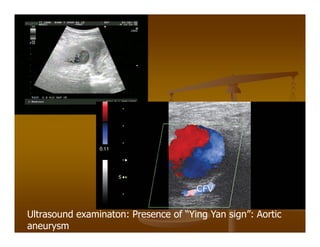

55 yo male patient with abdominal pain and

back pain

Ultrasound examinaton: Presence of “Ying Yan sign”: Aortic

aneurysm